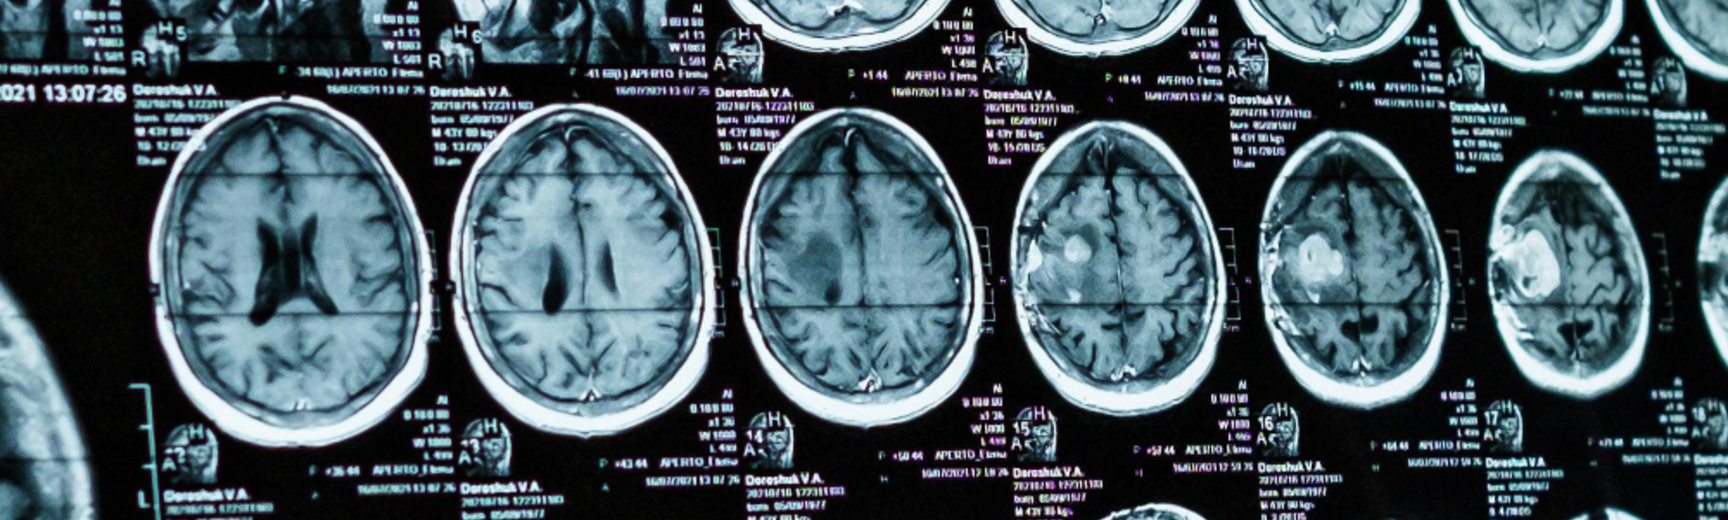

The Terri Schiavo case illustrates the heated controversy surrounding brain-damaged patients with disorders of consciousness. Some patients have suffered such severe brain damage that they have completely lost the capacity to be aware of themselves or their environment. This is known as the vegetative state. But patients with what is now known as the ‘minimally conscious state’ still possess at least rudimentary and intermittent awareness. These conditions raise difficult ethical questions. Is it in the interest of the patient to continue living in these conditions? Is it ever permissible to let such patients die rather than keep them alive at great cost? Or is life always sacred, and must never be ended, even if living is no longer a benefit to the patient? Can we be confident that awareness is really missing, and can we use neuroimaging to identify consciousness, or even communicate with seemingly non-conscious patients? If consciousness is present, but only in a rudimentary way, would this be a good thing, or rather make things worse, because only conscious patients can suffer?

Kahane, G., Skene, L., Wilkinson, D. and Savulescu, J. (2009) 'Neuroimaging and the Withdrawal of Life-Sustaining Treatment from Patients in the Vegetative State', Medical Law Review, Vol: 17(2) [open access]

Levy, N., (2009), 'What Difference does Consciousness Make?' Monash Bioethics Review, Vol: 28 (2) [open access]Wilkinson, D., Kahane, G., Horne, M. and Savulescu, J. (2009), 'Functional neuroimaging and withdrawal of life-sustaining treatment from vegetative patients', Journal of Medical Ethics, Vol: 35 pp. 508-511 [open access]